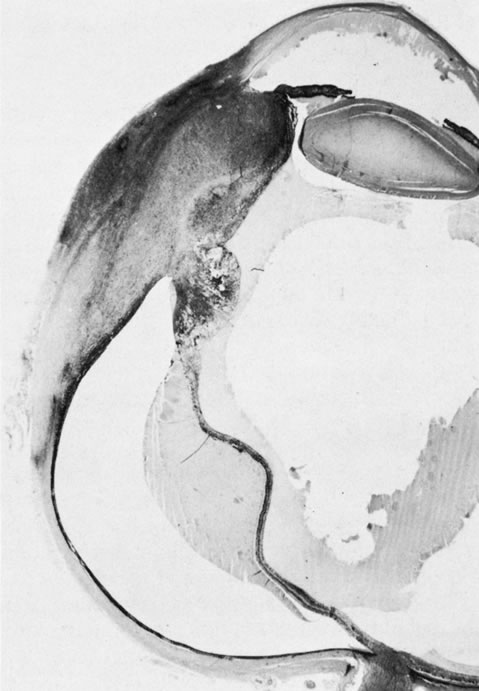

73. Schanzlin D, Robin J, Erickson G et al:, Histopathologic and ultrastructural

analysis of congenital corneal staphyloma. Am J Ophthalmol 95:506, 1983.

74. Leff S, Shields JAugsburger J et al: Congenital corneal staphyloma:

Clinical, radiological and pathologic correlation. Br J Ophthalmol 70:427,

1986.